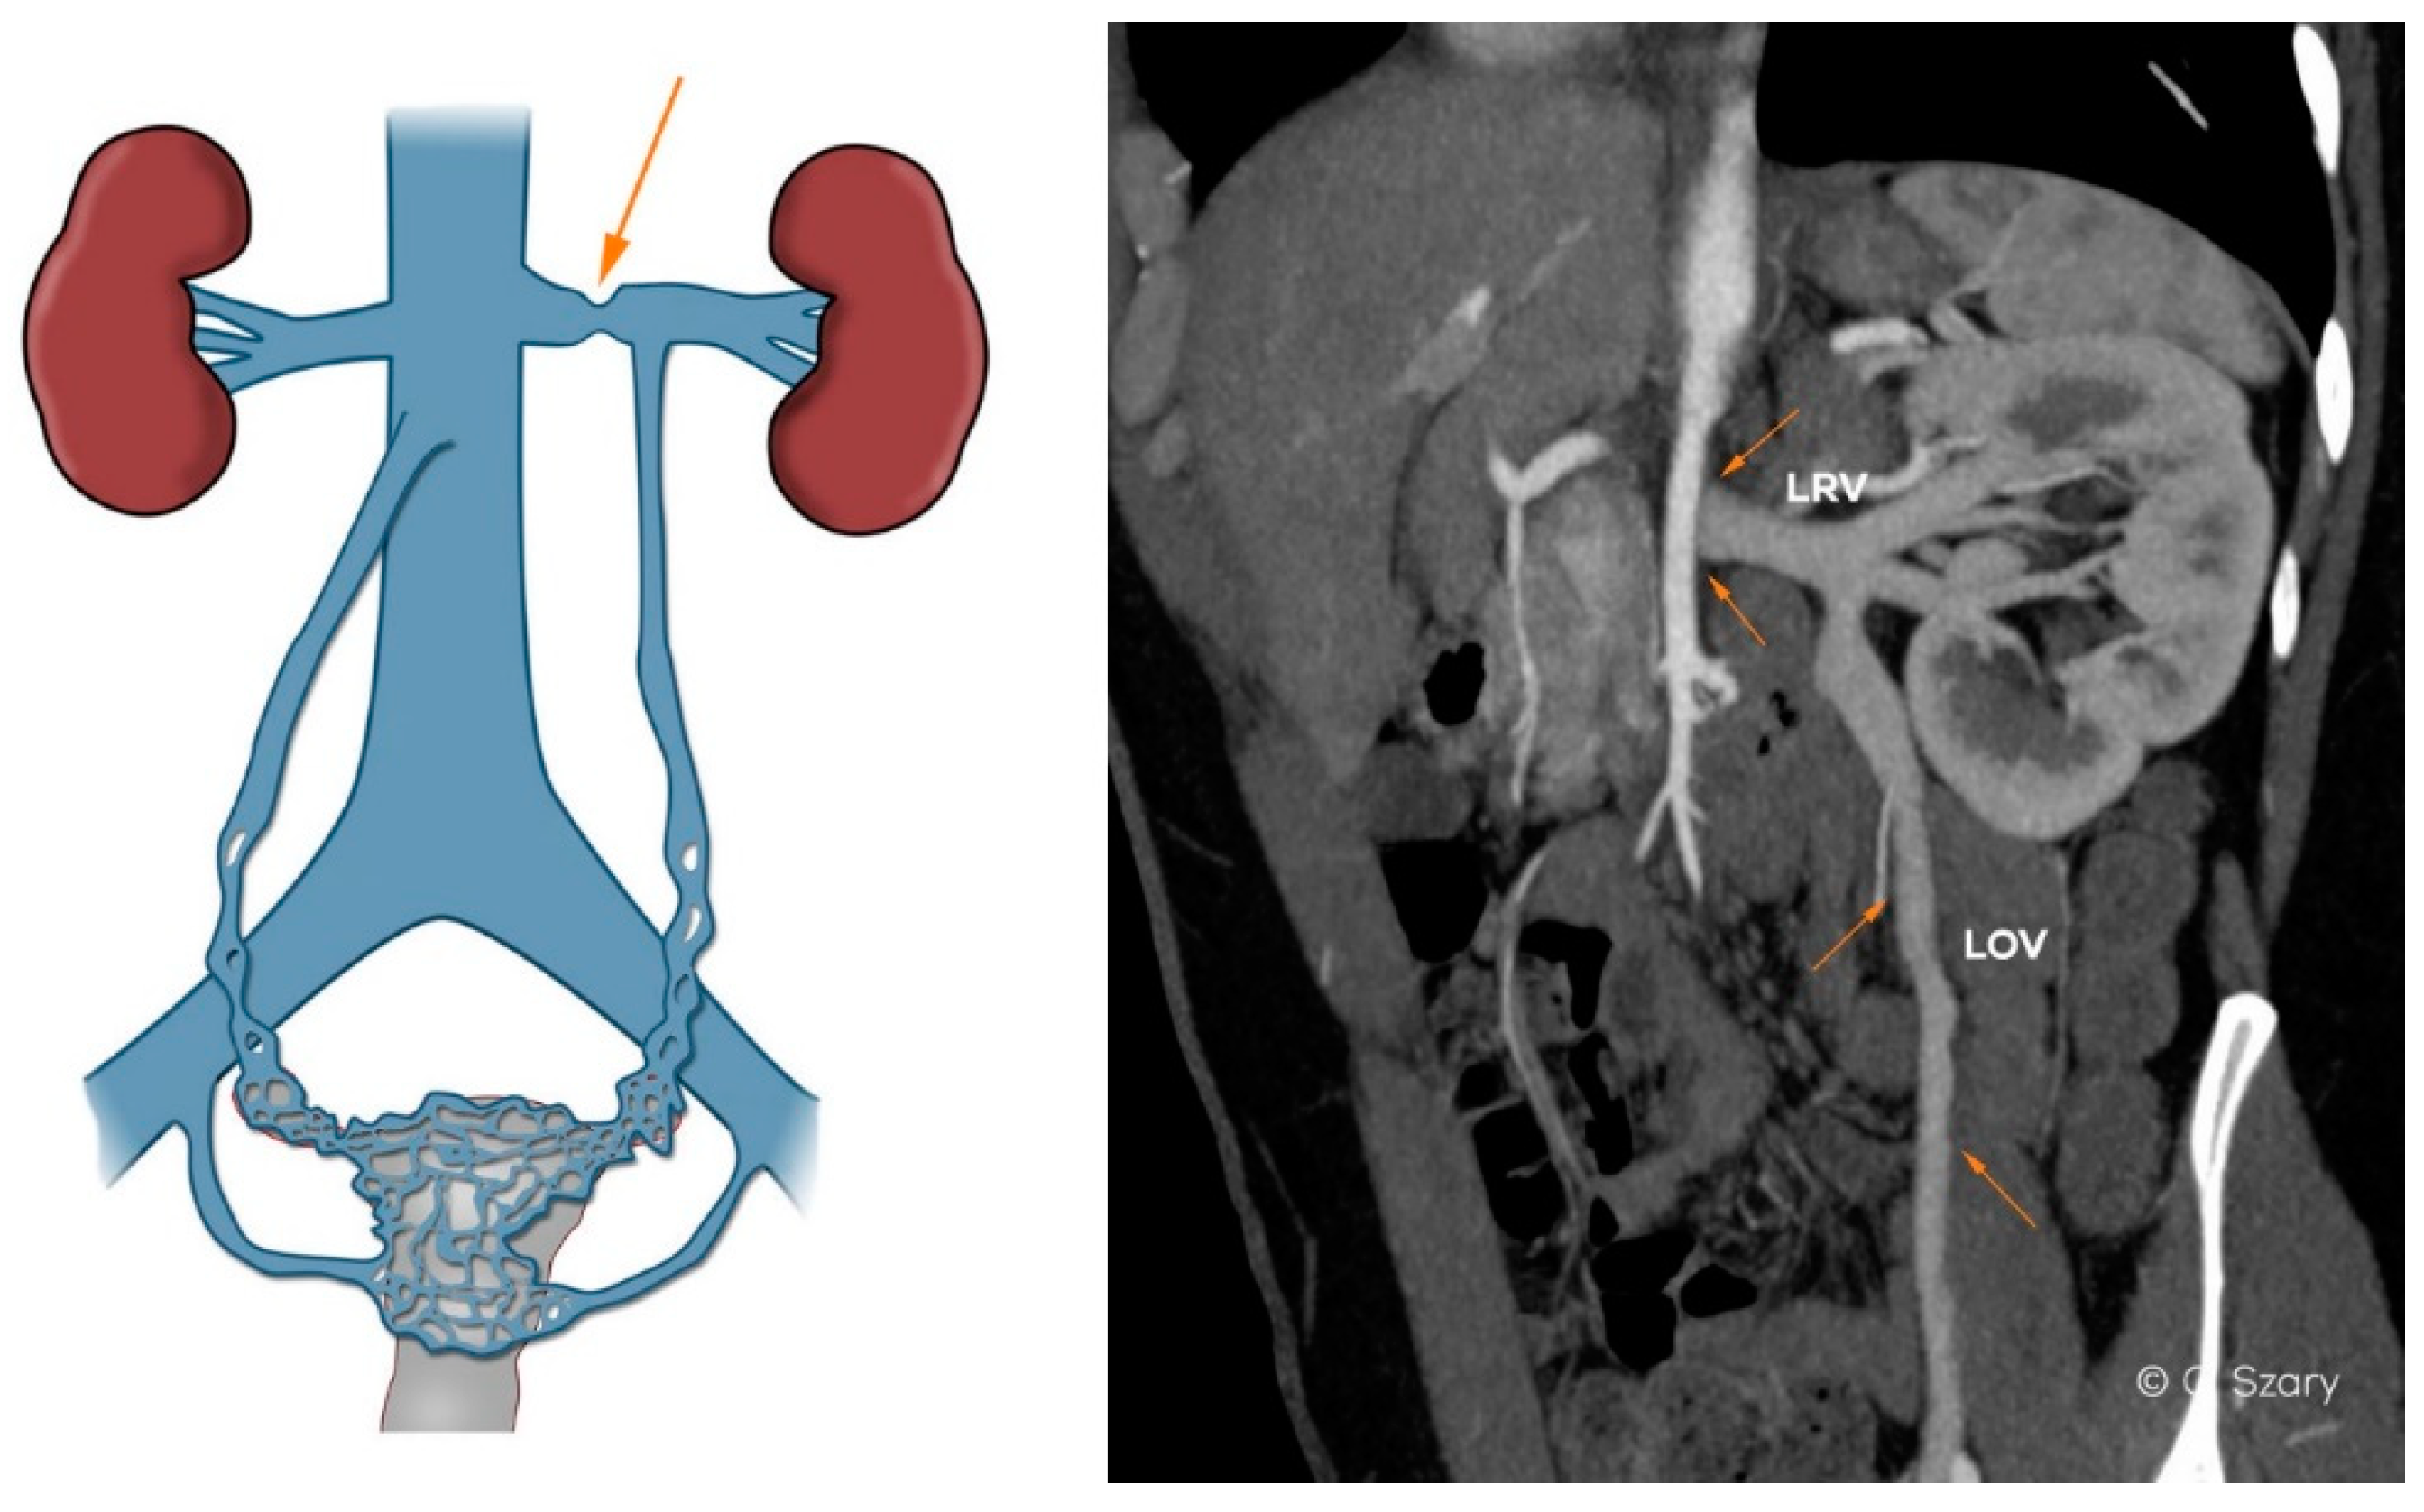

Figure 5.

Typical anatomy of nutcracker syndrome. Insufficiency of LOV on computed tomographic venography (CTV) image.

Anatomical variations and significant developmental variants may affect the female pelvic venous system even in teenagers, before any pregnancy takes place. These variations may increase intravenous blood pressure, with reversed flow and/or collateral circulation bypassing the vein obstruction or compression. Most often these changes concern LRV-LOV axis involving the ascending lumbar vein or internal iliac veins (Figure 6).

Figure 6.

CTV and intra-interventional phlebographic images of nutcracker phenomenon (LRV compression by superior mesenteric artery, dilated venous collaterals from hilar veins of left kidney (orange arrows), insufficient LOV).

In the assessed material, it was found that the most common anatomical phenomena and variations, significantly affecting morphology and hemodynamics of the ovarian axes, are:

- −

- narrow distal segment of the LRV (developmental variant);

- extrinsic compression of the LRV by the superior mesenteric artery (SMA)–typical of the nutcracker phenomenon;

- atypical drainage of the right ovarian vein into the trunk of the right renal vein (Figure 7).